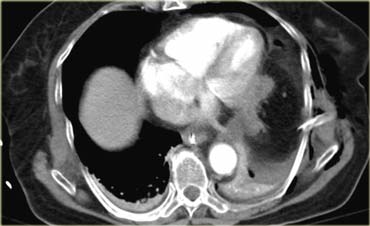

Bên trái là hình ảnh của một bệnh nhân có tổn thương bên phải.

Trên phim X-quang ngực, hình ảnh trông như thể chỉ đơn thuần là nâng cao vòm hoành hoặc có thể có tràn dịch màng phổi dưới phổi.

Cũng có thể đây là liệt cơ hoành từ trước.

Bây giờ hãy tiếp tục với các hình ảnh CT.

Hãy mô tả các dấu hiệu bên trái rồi tiếp tục.

Hình ảnh axial cho thấy vùng mờ trên phim X-quang ngực thực chất chính là gan.

Khi theo dõi đường bờ của gan, có hình dạng bất thường (mũi tên vàng).

Có sự gián đoạn của trụ cơ hoành, đây là dấu hiệu không đặc hiệu (mũi tên xanh nhỏ).

Trên hình axial, có hình ảnh lõm vào mặt sau của gan do máu trong lồng ngực.

Trên tái tạo MPR mặt phẳng sagittal, hình ảnh lõm vào của gan và ‘dấu hiệu cổ thắt’ được thể hiện rõ ràng.